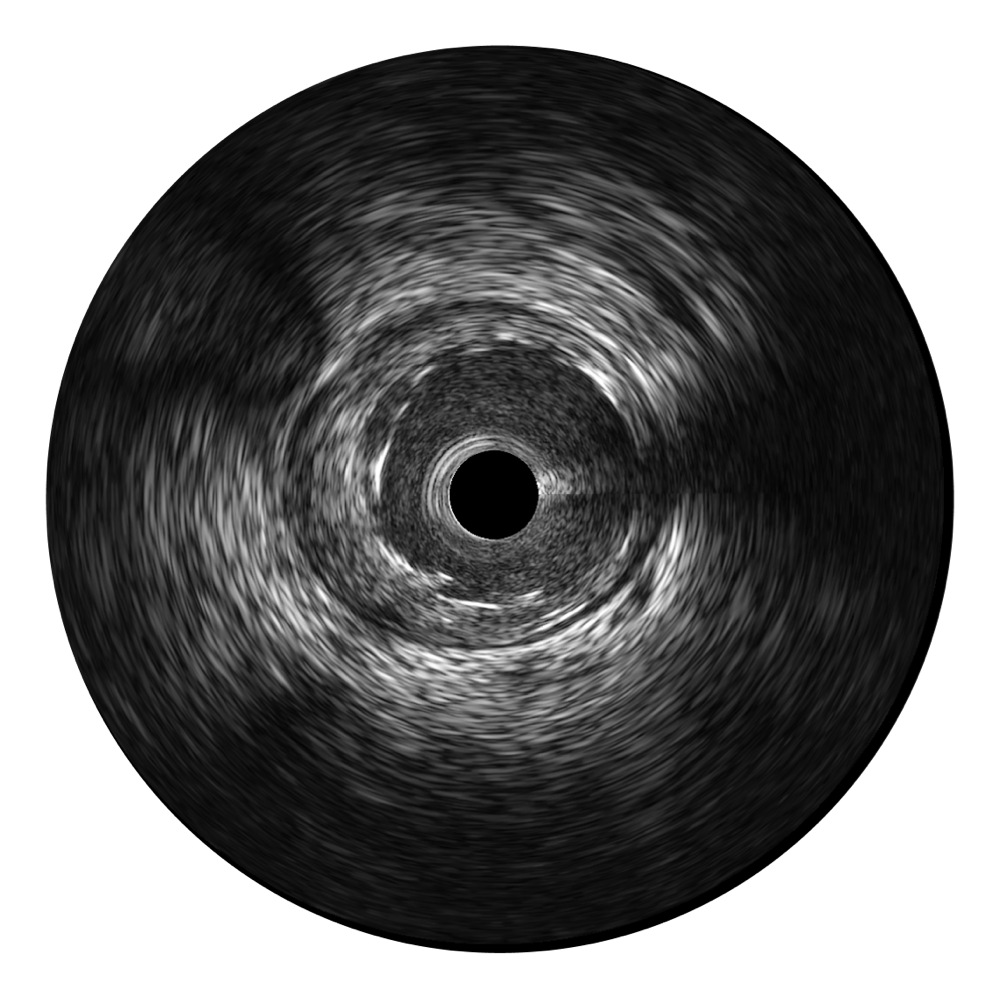

• 球速体育入口宽频IVUS图像

• 传统IVUS图像

对比传统IVUS导管成像,球速体育入口宽频IVUS图像的近场支架梁显影更细腻,远场中膜外血管仍清晰可辨,兼顾远中近,兼顾分辨力与穿透深度